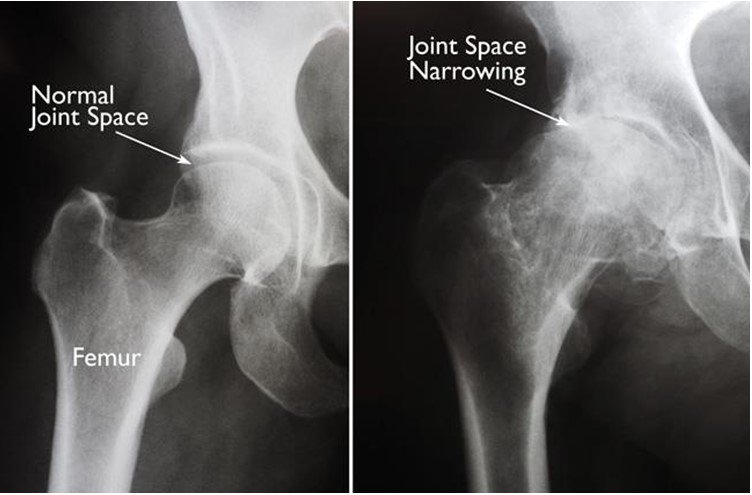

• Osteoarthritis. This is an age-related wear and tear type of arthritis.

• Osteonecrosis(Avascular Necrosis). Dislocation, neglected fracture, self medication with steroid tablets, alcohol consumption may limit the blood supply to the femoral head.